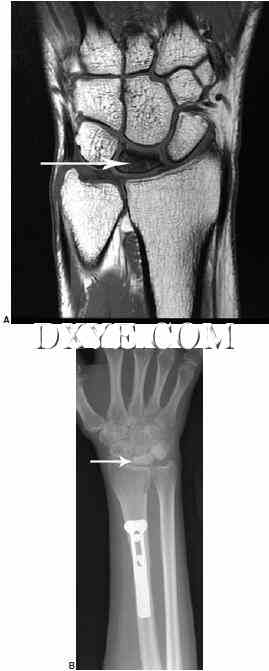

尺骨茎突骨折。 超过50%的桡骨远端骨折伴有尺骨茎突骨折,但并非所有的尺骨茎突骨折均需要修复。 手术干预取决于DRUJ的稳定性。 发现尺骨茎突基底骨折和位移大于2 mm的基底骨折会影响DRUJ的稳定性。 当根据放射照片的外观怀疑DRUJ不稳定时,对照正常的手腕检查DRUJ在中性,完全旋后和完全旋前的平移松弛。 一旦桡骨远端骨折已经修复,外科医生应该检查受伤的手腕并将其与正常侧进行比较。 如果DRUJ松弛,尤其是完全旋后,尺骨茎突修复。 可以使用克氏线,张紧带线或空心无头螺钉(图76.18)。 使用糖钳或Munster型夹板,将前臂在中性旋转下固定4至6周。

18.jpg

图 76.18.  延迟与尺骨茎突骨折不愈合DRUJ不稳定表现。A.术前X线片显示桡骨相对尺骨背侧半脱位,与尺骨茎突显示箭头移位。B.晚期术后X线片显示尺骨茎突与TFCC重新插入使用骨锚钢丝张力带。